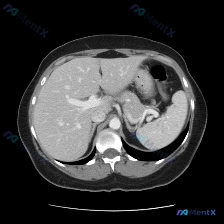

今天整理了一份上腹部增强CT的病例,关于脾脏结节的读片和鉴别思路,分享一下: 先看完整影像表现 这是一张上腹部增强CT横断面(软组织窗),对比剂显影良好,主要观察到两个核心异常: 1. 肝脏:肝左外叶、右后叶各见一个类圆形低密度灶,边界清、无强化,符合典型肝囊肿表现; 2. 脾脏:脾实质内见一个类圆...